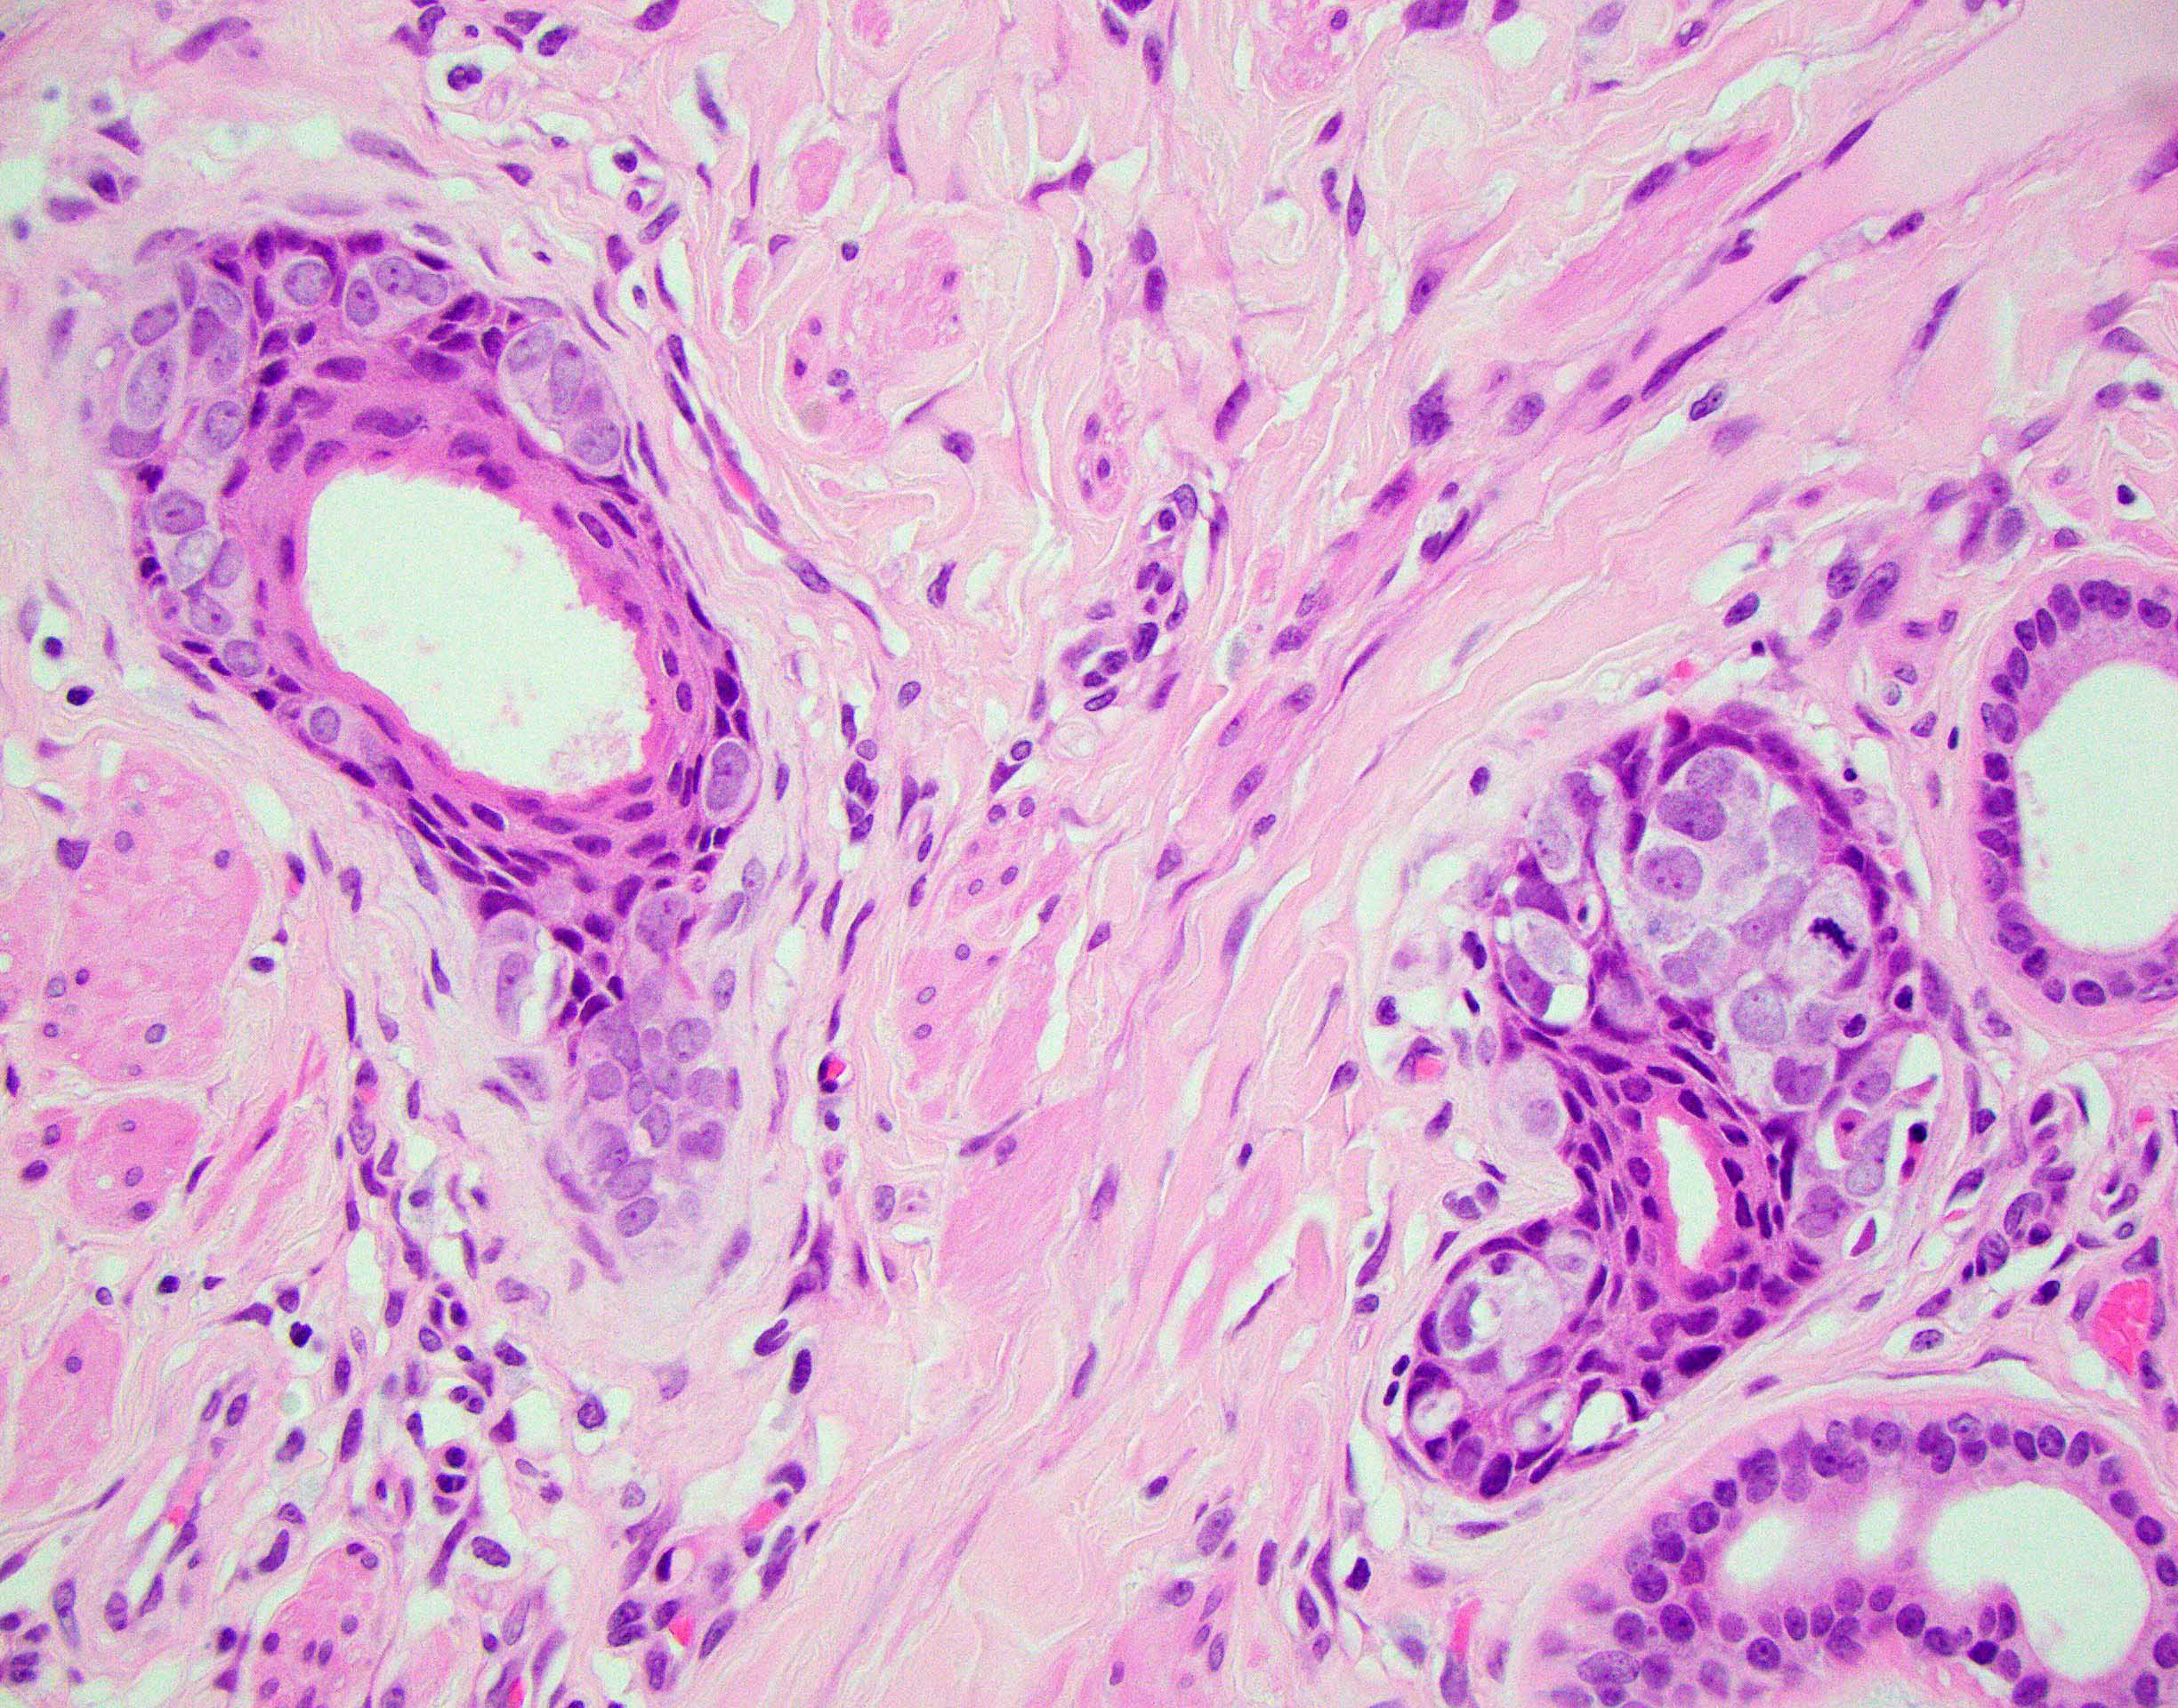

Microscopic (histologic) description

- Paget cells are enlarged polygonal epithelial cells with abundant pale cytoplasm, large nuclei and small to prominent nucleoli

- Intracytoplasmic mucin is frequently present

- Intracytoplasmic melanin pigment may be present (rare)

- Rarely, gland formation may be seen

- Predominantly located in the basal and parabasal portions of the squamous epithelium

- Extends upward as single cells or in small clusters

- Commonly involves the epithelium of skin adnexa

- Basal layer keratinocytes are preserved but may appear compressed by the tumor cells (Histopathology 2006;48:723)

- Prominent host inflammatory response in the superficial dermis is frequently seen

- Dermal invasion

- Single cells or small groups of cells infiltrating the dermis with an associated desmoplastic reaction

- Groups of cells may form glandular structures

- May be associated with dense dermal inflammatory response

Microscopic (histologic) images

Contributed by Priya Nagarajan, M.D., Ph.D. and Lucy Ma, M.D.

A 66 year old woman presents with a pruritic plaque on the right labia majora of 2 years duration. She has no significant oncologic history. As her symptoms have not improved, a punch biopsy is performed (image shown above). A mucicarmine stain is positive within the tumor cells. Which of the following ancillary stains would also likely be positive in this tumor?

B. CK7. Given the history of a pruritic lesion of years in duration, along with the microscopic image of mucicarmine positive cells percolating through the epidermis, the diagnosis is most likely extramammary Paget disease, which is strongly CK7 positive. Answer D is incorrect because while melanoma is certainly in the differential diagnosis given the microscopic image, it would not be consistent with mucicarmine positivity; therefore, HMB45, a melanoma marker, is incorrect. Answer C is incorrect because while in theory high risk HPV ISH could potentially be positive in Paget disease of the vulva secondary to a HPV dependent cervical adenocarcinoma, primary vulvar Paget disease is far more common. Answer A is incorrect because CK5/6 is a high molecular weight cytokeratin, which stains squamous cells, not glandular cells.